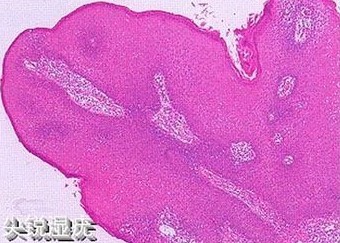

尖锐湿疣是一种危害性很大的性传播疾病,尖锐湿疣的发病率还在不断的上升当中,越来越多的人受到尖锐湿疣的困扰,尖锐湿疣具有很强的传染性、复发性和潜伏性,是性传播疾病中的一个大BOSS,那么为什么会出现尖锐湿疣的呢?下面上海九龙男科医院的医生将为大家讲解.